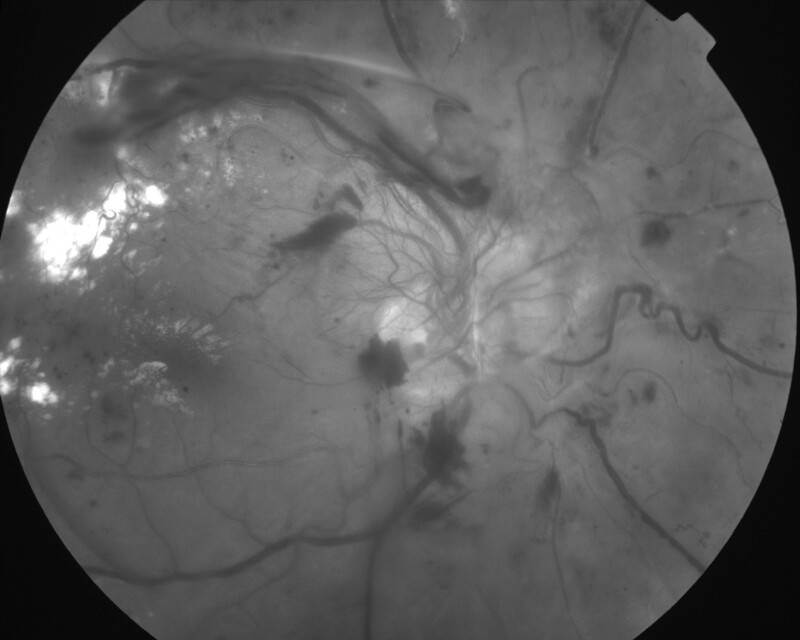

RETINOPATHIE DIABETIQUE PROLIFERANTE